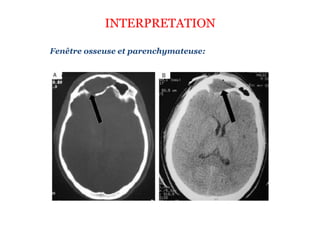

INTERPRETATION

Fenêtre osseuse et parenchymateuse: